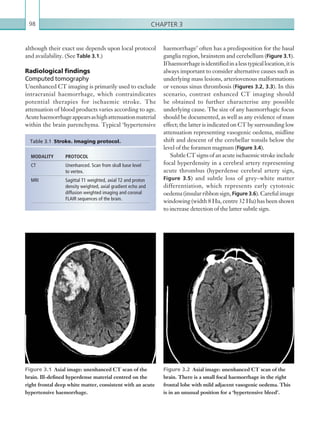

An understanding of the anatomy of the lung is

necessary to appreciate the spectrum of abnormality

seen in pulmonary oedema on both plain films and

CT. The secondary pulmonary lobule is the most

basic unit of pulmonary structure and is bordered

by a surrounding septum of connective tissue. It

is comprised of multiple acini (responsible for gas

exchange) with a central terminal bronchiole and

centrilobular artery. The peripheral septum contains

both the pulmonary veins and lymphatics, although

there is another central lymphatic network that courses

centrallythroughthesecondarypulmonarylobulewith

the bronchovascular bundle. Excess fluid can fill both

thealveolarairspaces(resultingingroundglassopacity,

whichcanprogresstoconsolidation)andthepulmonary

ACUTE PULMONARY OEDEMA

Chapter 118

interlobular septal thickening and visualisation of the

secondary pulmonary lobule (Figures 1.20a, b). This,

in combination with ground glass opacity, may form a

‘crazy paving’ appearance. This has a wide differential

diagnosis, which includes:

•	 Alveolar proteinosis.

•	 Oedema (heart failure/ARDS).

•	 Pulmonary haemorrhage.

•	 Infection (e.g. mycoplasma, Legionella,

Pneumocystis carinii/jiroveci pneumonia).

•	 Organising pneumonia.

•	 Acute interstitial pneumonitis/non-specific

interstitial pneumonitis.

As PCWP continues to increase, alveolar oedema will

occur, appearing as multifocal areas of ground glass and

airspace opacity in perihilar and dependent regions of

the lungs (Figure 1.21).

interstitium (resulting in smooth interlobular septal

thickening).

Interpretation of chest plain films should begin

with an assessment of the quality and radiographic

technique. Anterior-posterior studies can overestimate

the size of the cardiac silhouette due to X-ray beam

divergence. Supine images, as opposed to erect images,

cancauseredistributionofbloodtotheupperzonesand

widening of the vascular pedicle, important signs of left

ventricularfailureandpulmonaryvenoushypertension,

respectively. Poorly inspired images (6 anterior ribs)

can cause crowding of the pulmonary vasculature

and apparent lung congestion. Therefore, a PA chest

radiograph is the best for identifying the appropriate

features.

The spectrum of findings seen on both plain films

and CT in pulmonary venous hypertension can be

correlated with a progressive increase in PCWP. A

mild increase in PCWP results in upper lobe blood

diversion. As PCWP increases, additional findings

such as peribronchial cuffing, loss of vascular definition

and Kerley lines can be seen, all of which indicate

excess fluid in the interstitium (Gluecker et al., 1999)

(Figure 1.19). On CT, the normal interstitium should

be imperceptible. Excess fluid can result in smooth

Figure 1.19  AP portable chest radiograph. Fluid

can be seen in the horizontal fissure, as well as within

the interstitium along the periphery of the thorax.

There is also loss of vascular definition due to venous

hypertension.